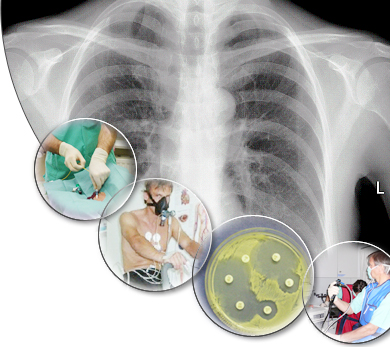

Візитною карткою лікарні є Міський пульмонологічний центр – провідна установа регіону, до складу якого входять: консультативний пульмонологічний кабінет поліклініки, два пульмонологічних відділення стаціонару, торакально-хірургічне відділення, відділення анестезіології з палатами інтенсивної терапії, допоміжні підрозділи лікарні.

Основними задачами Центру є надання цілодобової спеціалізованої, висококваліфікованої лікувально-діагностичної і консультативної допомоги хворим із захворюваннями бронхолегеневої системи, плевральної порожнини та грудної стінки. В торакально-хірургічному відділенні виконуються різноманітні хірургічні втручання від атипових сегментарних резекцій легенів до травматичних, розширених, технічно складних та довготривалих за часом пульмонектомій при онкологічних захворюваннях легень. До задач Центру входить також організаційно-методична функція по плануванню діяльності пульмонологічної служби міста.